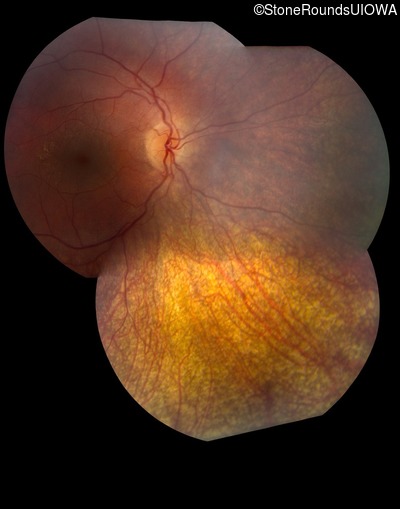

Fundus Montage - Right -

No Light Perception

Exemplar

Fundus Montage - Left -